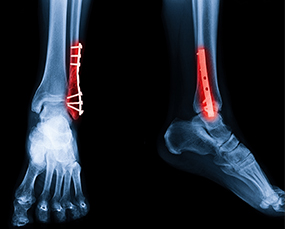

Advanced Ortho & Trauma Solutions

From consultation to post-operative care, our clinic in Noida ensures accurate treatment plans and superior outcomes in orthopedic and trauma care.